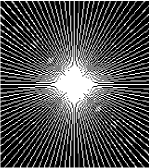

All the experiments are implemented on a Windows workstation with Intel Core i9 CPU at 3.3GHz and an Nvidia GTX-1080Ti GPU with 11GB of graphics card memory via TensorFlow Abadi et al. (2016). The parameters in the proposed network are initialized by using Xavier initialization Glorot and Bengio (2010). We trained the meta-learning network with four tasks synergistically associated with four different CS ratios: 10%, 20%, 30%, and 40%, and test the well-trained model on the testing dataset with the same masks of these four ratios. We have 300 training data for each CS ratio, which amount to total of 1200 images in the training dataset. The results for and MR reconstructions are shown in Tables 5.4 and 5.4 respectively. The associated reconstructed images are displayed in Figures 1 and 3. We also test the well-trained meta-learning model on unseen tasks with radio masks for skewed ratios: 15%, 25%, 35%, and random Cartesian masks with ratios 10%, 20%, 30% and 40%. The task-specific parameter for the unseen tasks are retrained for different masks with different sampling ratios individually with fixed task-invariant parameters . In this experiments, we only need to learn for three skewed CS ratios with radio mask and four regular CS ratios with Cartesian masks. The experimental training proceed on less data and iterations, where we performed on 100 MR images with 50 epochs. For example, for reconstructing MR images with CS ratio 15% radio mask, we fix the parameter and retrain the task-specific parameter on 100 raw data with 50 epochs, then test with renewed on our testing data set with raw measurement that sampled from radio mask with CS ratio 15%. The results associated with radio masks are shown in Table 5.4 and 5.4, Figure 2 and 4 for and images respectively. The results associated with Cartesian masks are list in Table 5.4 and reconstructed images are displayed in Figure 5.

In general supervised learning, training data need to be in the same or similar distribution, heterogeneous data exhibits different structure variations of features which hinders CNNs to extract features efficiently. In our experiments, raw measurements sampled from different ratios of compressed sensing display different levels of incompleteness, these undersampled measurements do not fall in the same distribution but they are related. Different sampling masks are shown at the bottom of Figure 1 and 2 may have complemented sampled points, in the sense that some of the points which sampling ratio mask does not sample have been captured by other masks. In our experiment, different sampling masks provide their own information from their sampled points so that four reconstruction tasks help each other to achieve an efficient performance. Therefore, it explains the reason that Meta-learning is still superior to conventional learning when the sampling ratio is large.